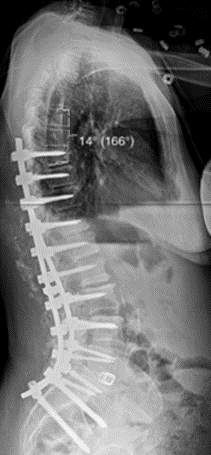

3.降低内固定硬度和减少融合区内固定数量

(1)降低内固定棒的硬度,用钛合金代替钴铬合金棒;

(2)全节段椎弓根螺钉固定改用间隔置钉固定;

(3)适当降低固定融合区内固定强度。

图25 降低内固定硬度和减少融合区内固定数量